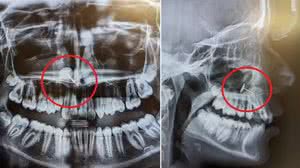

Mãe leva filha adolescente para raio X odontológico e fica chocada com o que descobre